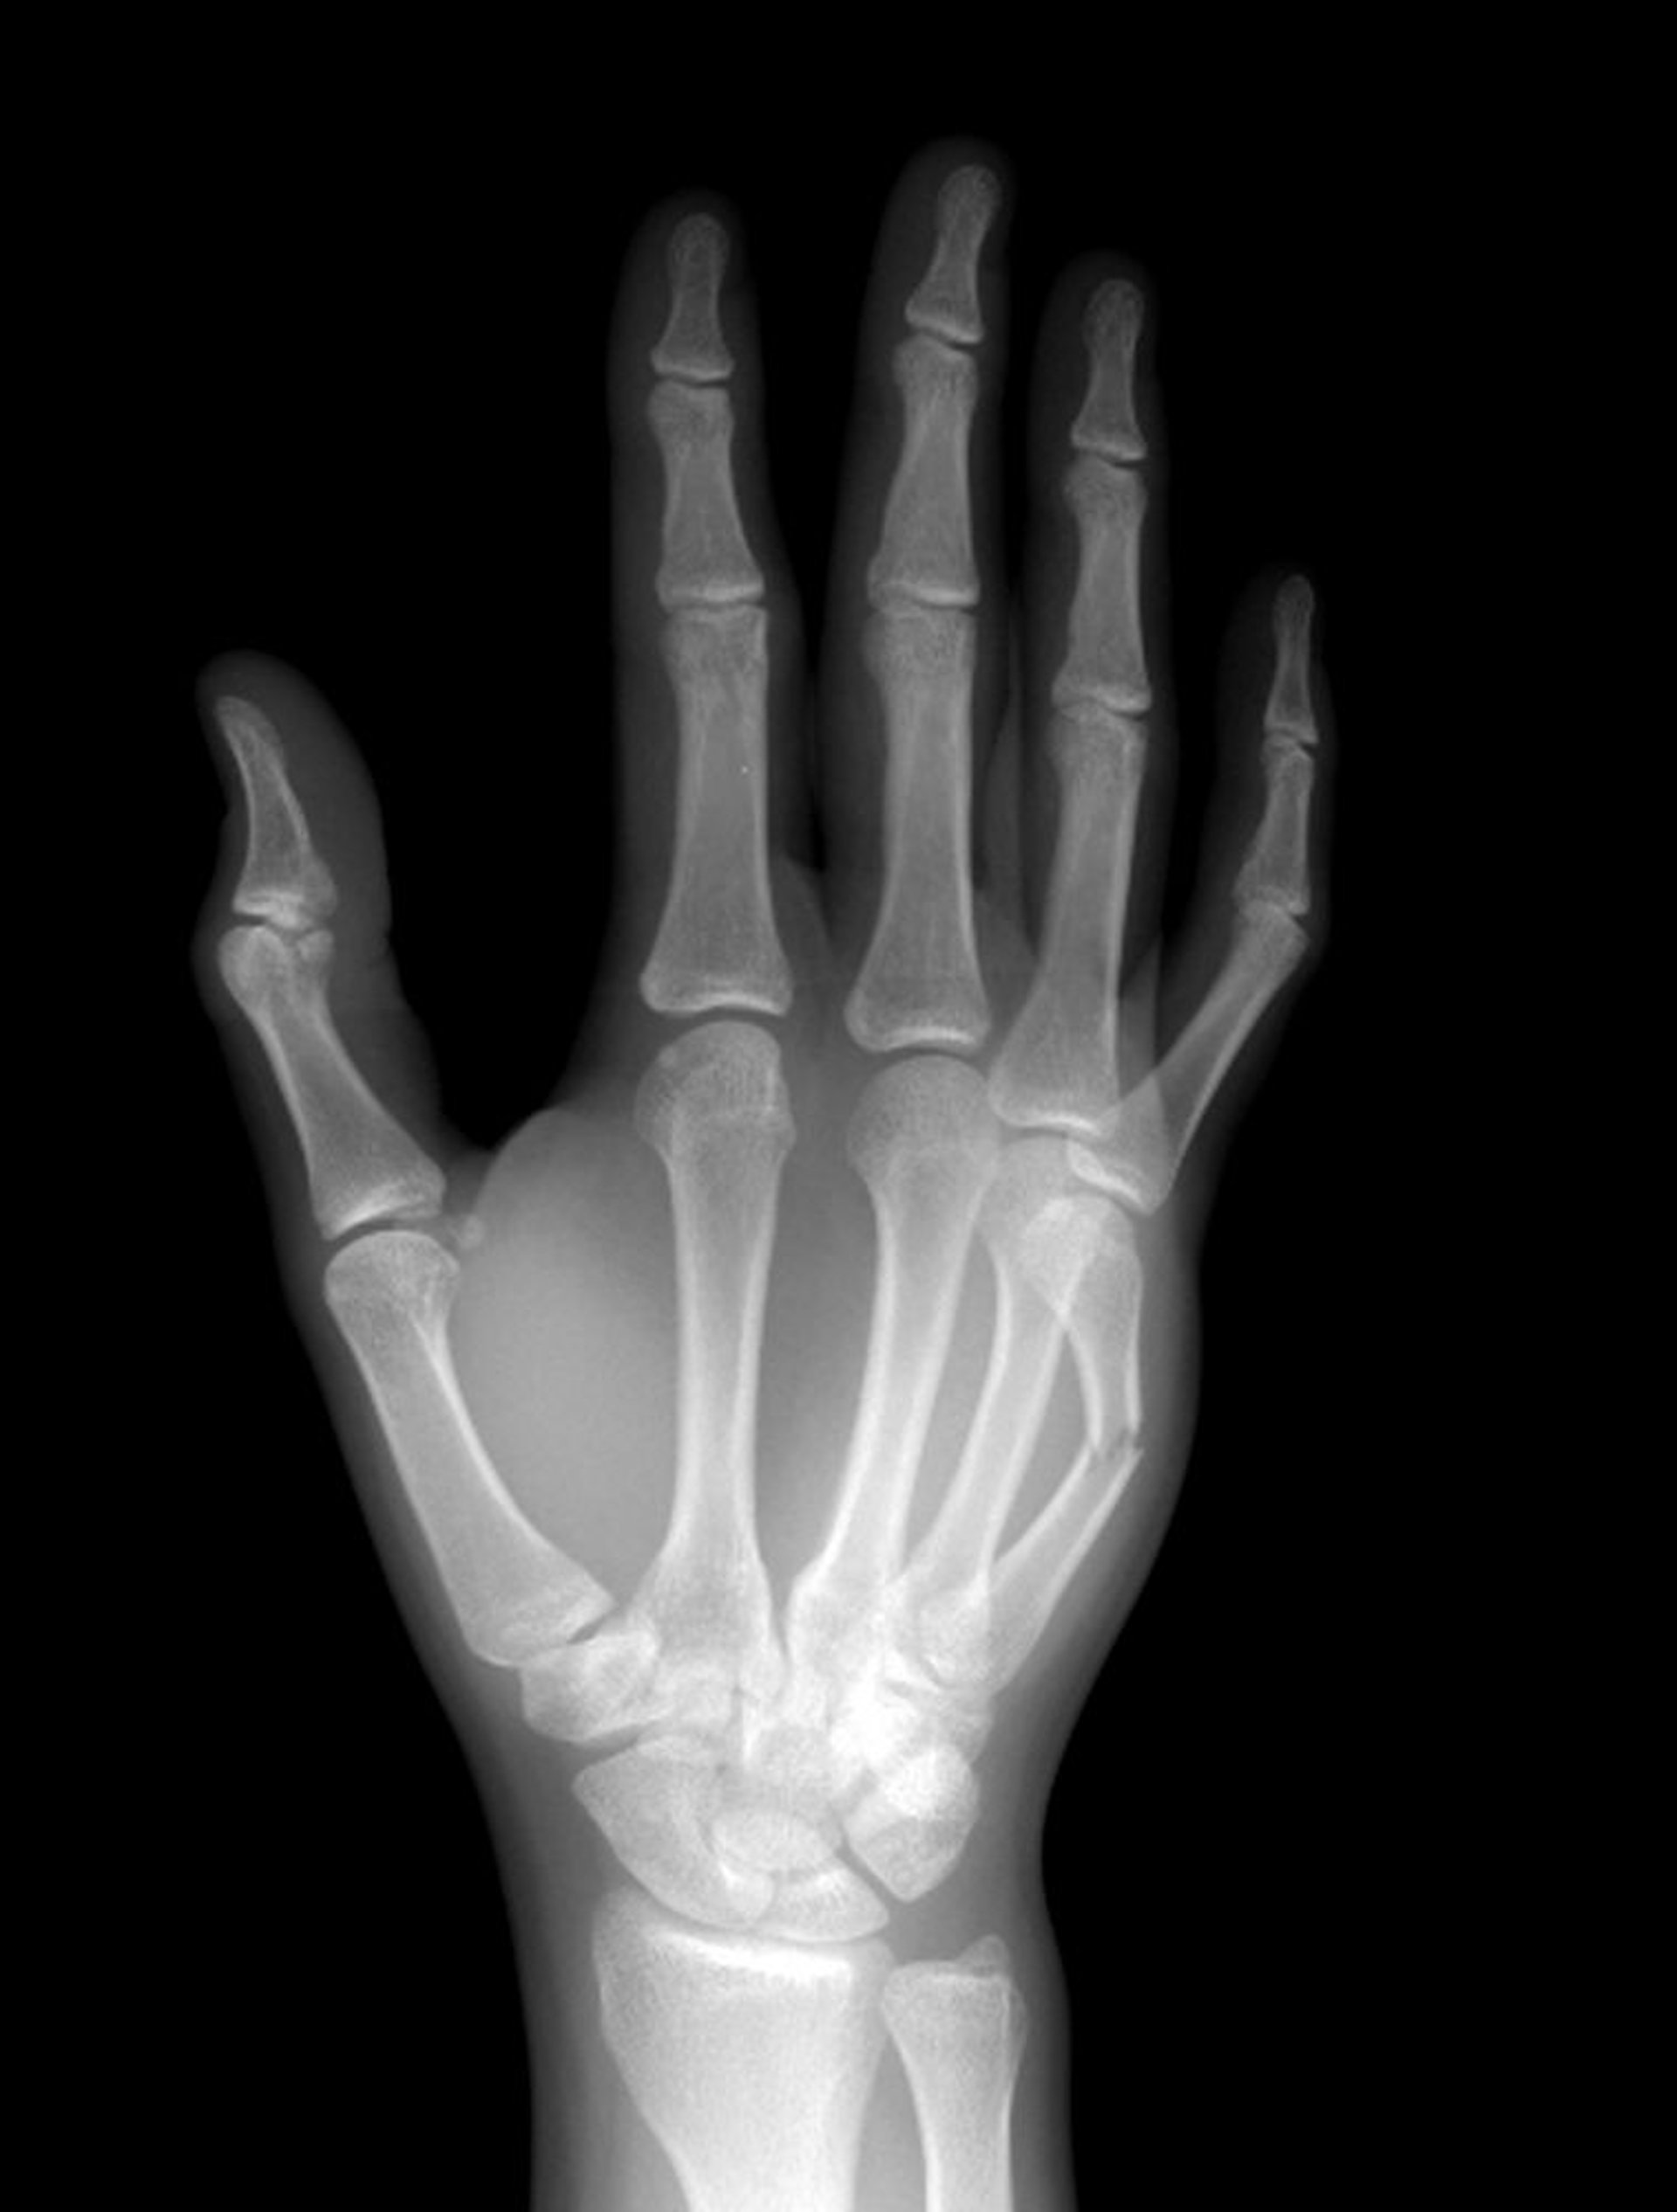

中手骨頸部骨折

第5中手骨頸部が骨幹部で骨折している。